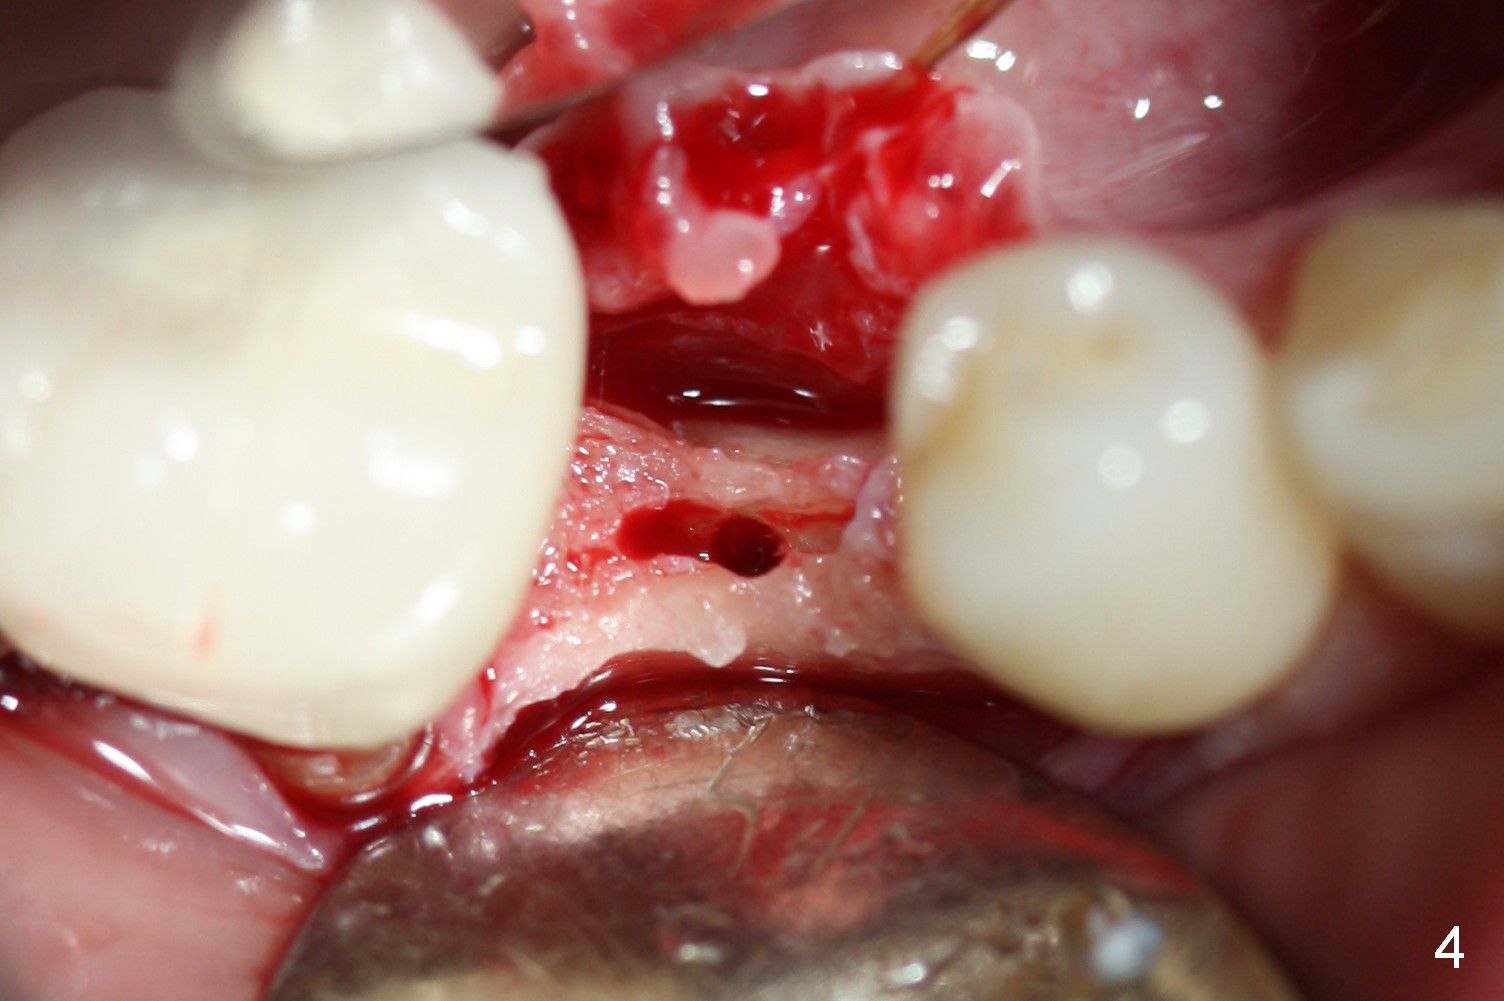

Preop photo shows the distal inclination of the tooth #28 (Fig.1).  The distal surface of the latter is reduced before incision for implant placement at #29 (Fig.2).  The buccolingual width is approximately 4 mm, as compared to 3 mm implant positioner (Fig.3).  After 1.2x10 mm osteotomy (Fig.5), the mesiodistal cortical bone is removed with a small high-speed fissural bur (Fig.4).  When a 2.5x12(2) mm 1-piece implant is placed (Fig.6), there is no buccal (Fig.7) or lingual plate perforation.  There is no postop paresthesia.  There is mild bone loss distal 4 months postop (Fig.8 *).  Take photos before and after permanent crown cementation to show increase in ridge width after bone graft and improvement in gingival health after provisional modification.  Take PA and/or BW post cementation to show that the distal bone resorption (Fig.8 *) is partially due to angulation.  No continuous bone loss 15 months post cementation (Fig.9).  There is mild bone resorption mesially 2 years 3 months post cementation (Fig.10).  The soft and hard tissues remain healthy 4 years 3 months post cementation (Fig.11,12).